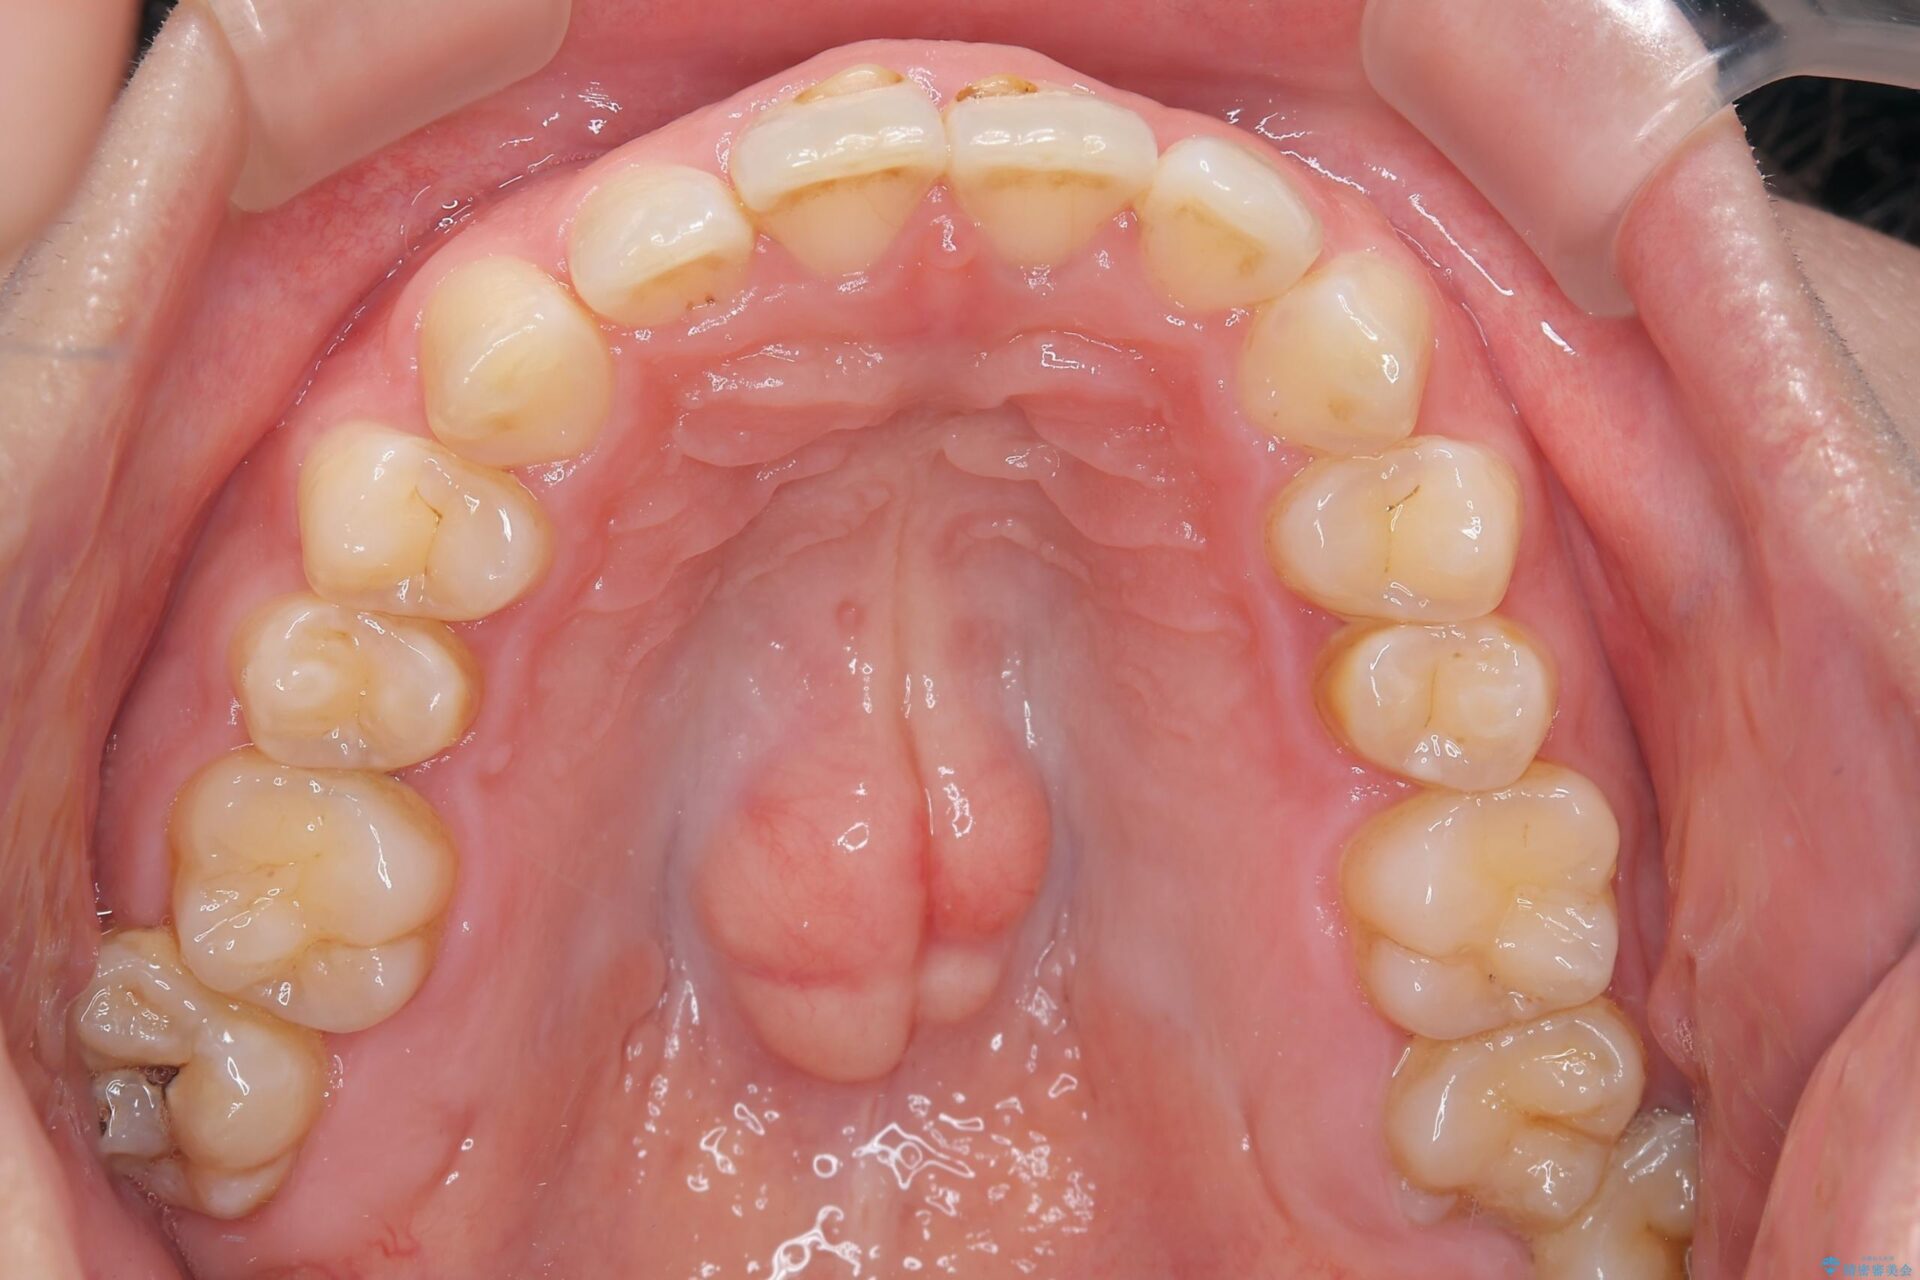

下の歯のガタつきが気になるとご来院された患者様です。

下の歯のがたつきと右の奥歯の噛みあわせ改善する治療計画を立てました。

まず右側臼歯部の咬合改善のために、臼歯部のみ部分的なワイヤー矯正を行い、咬合改善がみられてからインビザラインにて全体的な矯正を行なっていくこととします。

下の前歯のがたつき改善にはIPR(歯と歯の間を削る処置)を行いました。